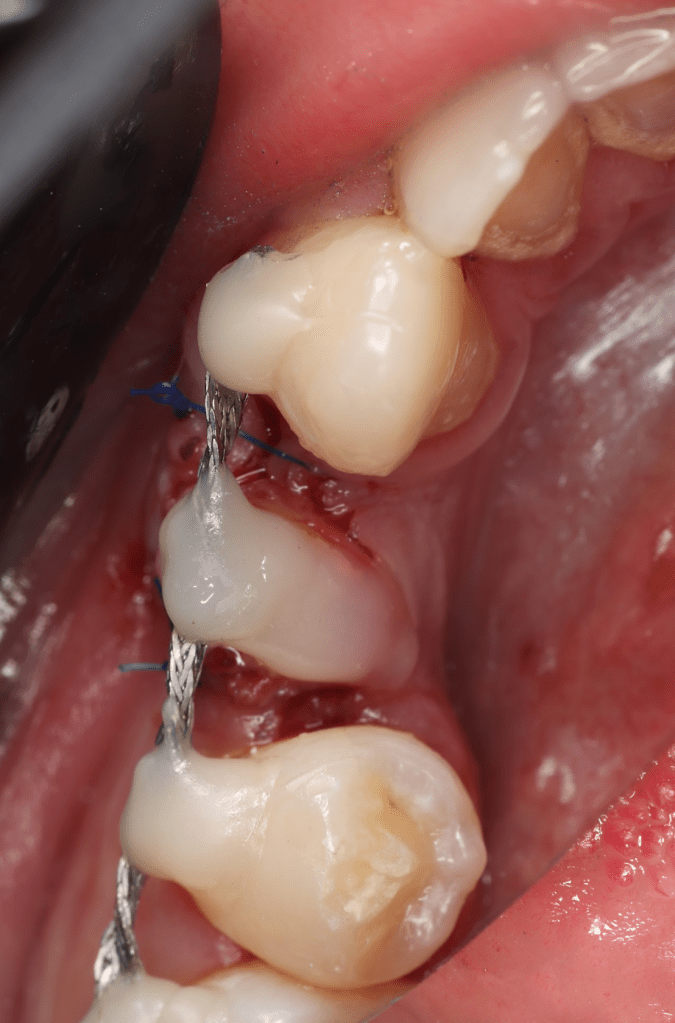

Reco pre-endo gingivectomái, pared yuxtaosea